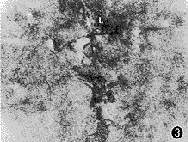

图2 示长足突放大,N示细胞核,P示色素颗粒,L示足突 ×14000

图3 示短足突末梢放大(L),周围有大量Ⅰ型胶体金颗粒 ×40000

2.足突细胞周围胶原分布:在细胞足突与胶原接触区域可见大量抗Ⅰ和Ⅲ型胶原抗体的胶体金颗粒(图3),两者相比,Ⅰ型胶原的阳性标记较为显著。此外,在胞膜形成内褶的区域也可见丰富的胶体金颗粒(图4)。